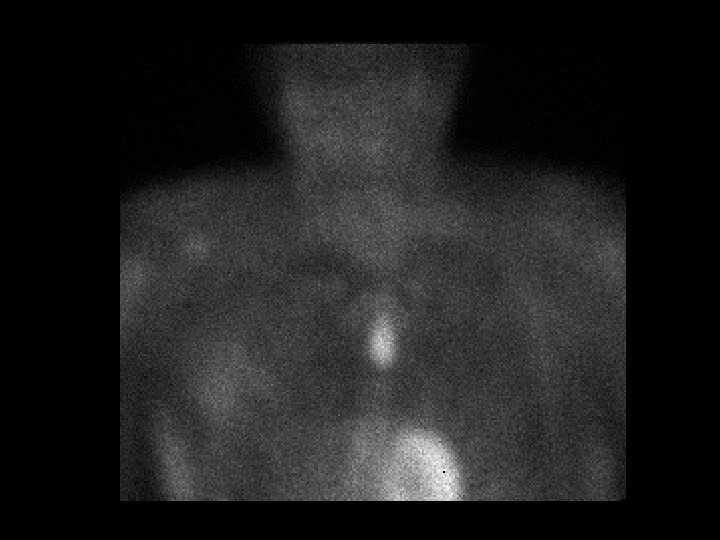

Ectopic parathyroid adenoma • Findings: – Delayed MIBI scan shows focal activity in the upper midline chest – Parathyroid scans MUST include a view of the chest for this reason • ddx: – NONE! – This is an Aunt Minnie!